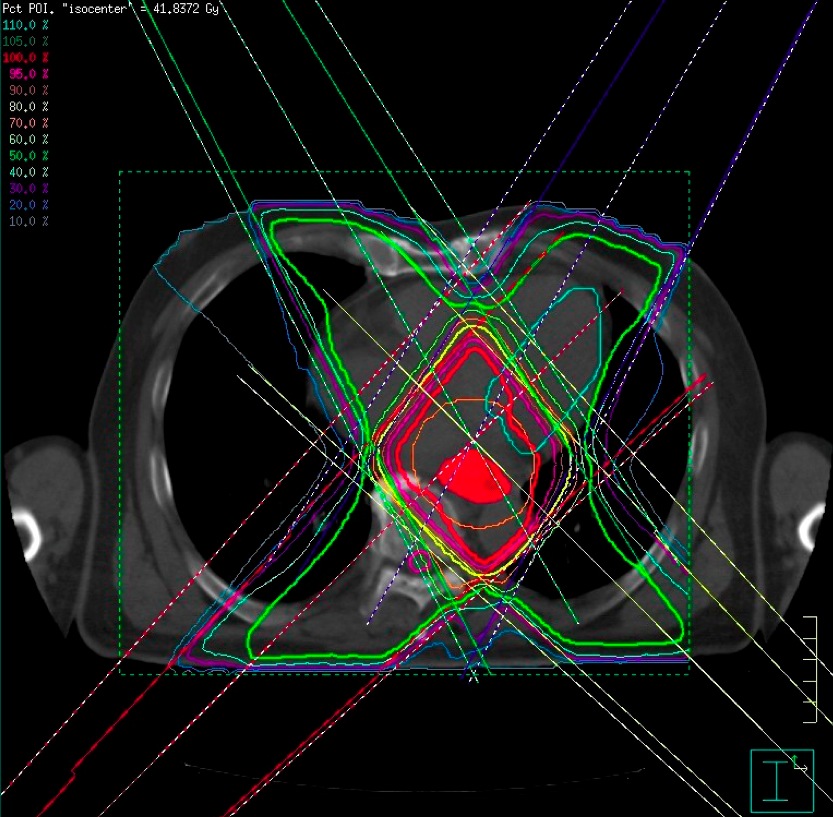

まず申し上げたいのは、最近の放射線治療は「がん」治療のかなでも副作用の少ない治療法とされています。それには多くの技術革新があっての結果ですが、一般にピンスポイント照射とも呼ばれている高精度な三次元治療計画が最も重要な役割を果たしています。それは副作用のでやすい臓器を避けて病巣に放射線を集中照射する技術です。写真4をご覧ください。

赤い肺癌に放射線照射を行うときに最も注意しなければならないのは緑の脊髄です。画像情報を駆使して、脊髄障害を起こさずに肺癌病巣に照射する方法を事前に十分検討してから、最も良い方法を選んで実際の治療を行うのです。写真5は主に食道に放射線を集中しものですが、ここでは前後にある心臓と脊髄を避けて4方向から照射しています。この方法で癌病巣や脊髄・心臓にどの位の放射線があたるのかを写真6のようなグラフを描いて評価します。したがって、昔のコバルト治療時代の副作用とは比較にならないほど軽く済むことが多くなりました。それでも副作用には個人差があり、特に治療中に発生する早期反応は化学療法でも強まり、ある程度は我慢しなければならない場合もあるでしょう。さらに副作用に対応する腫瘍看護学も進歩しており、日常のケアが行き届くようになっていますので、何か辛いことがあれば医療スタッフに遠慮なく相談したほうがよいでしょう。